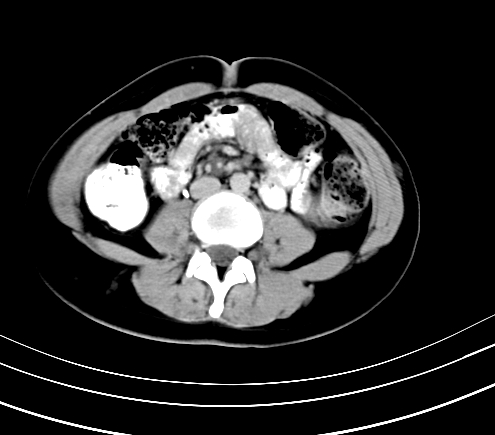

动脉期